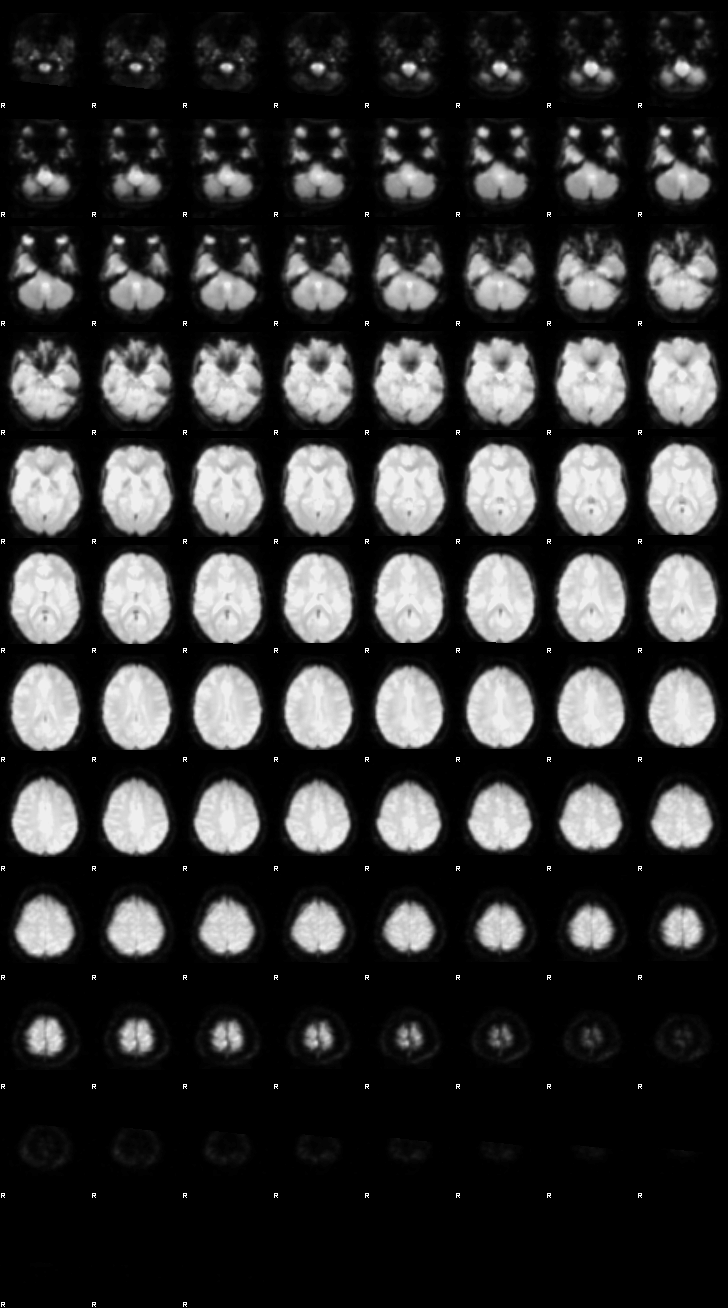

Let’s now display the thresholded activation maps. A voxelwise threshold of Z > 3.1 was applied, followed by cluster-level correction at p < 0.05 (corrected for multiple comparisons).

zstat1 - C1 (incongruent)

zstat2 - C2 (congruent)

zstat3 - C3 (incongruent-congruent)

display(Markdown("#### Incongruent"), rendered_thresh_zstats1)

Incongruent

display(Markdown("#### Congruent"), rendered_thresh_zstats2)

Congruent

display(Markdown("#### Incongruent-Congruent"), rendered_thresh_zstats3)

Incongruent-Congruent